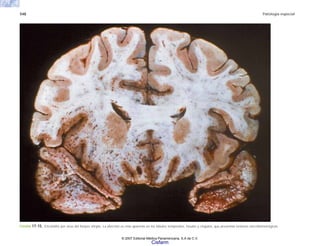

FIGURA 5-4. Asma bronquial. a) Aspecto sobredistendido de los pulmones en un caso fallecido durante un ataque agudo de asma. b) Corte trasnversal de un bronquio en el caso anterior,

que muestra la luz ocupada por material mucoso denso.